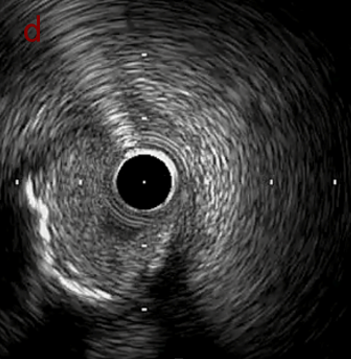

IVUS after OAS low speed 3回

IVUS imaging after low speed 3回

OAS low speedによる引きのsandingを3回行いIVUSを確認するとa-cでは心筋側側へのOASによる良好なbias変化と、それに伴いdの健常側への危険なbias変化を認めた。

そのためcでIVUSマーキングを行い、その点より引きで赤線のpinpoint OAS high speedを行い、dに関してはinjury回避のためにOASを当てない方針とした。

OAS low3